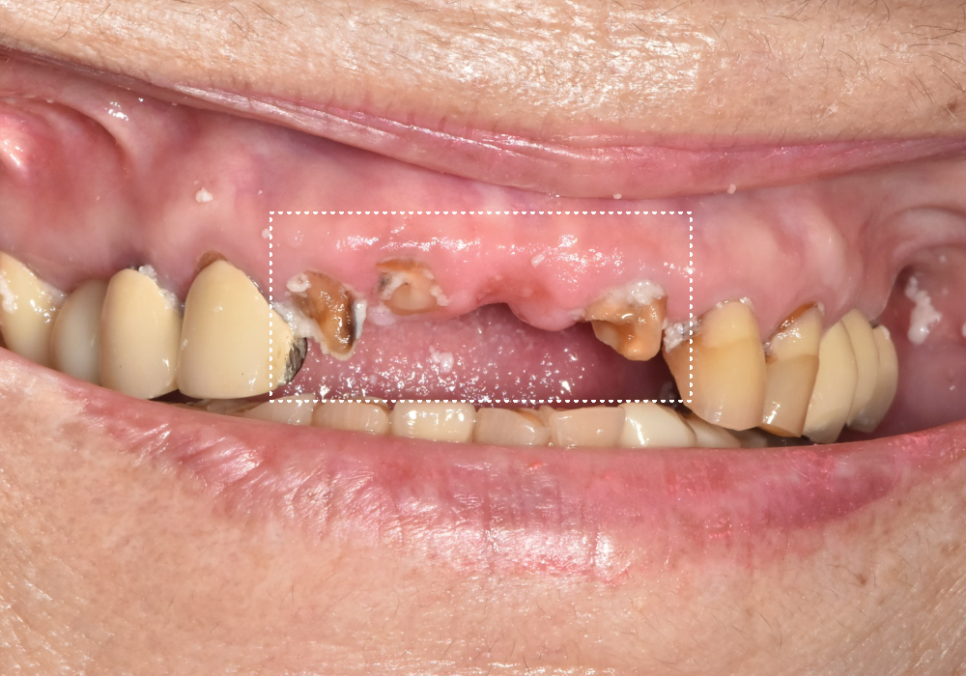

1년 뒤, 앞니와 브릿지가 부러져서 온 환자분

상일동 임플란트 심한 충치로 인한 치아 부러짐 해결한 사례

그로부터 1년 정도 지난 뒤,

환자분은 이번에는

앞니 쪽이 부러졌다고

다시 내원하셨습니다.

확인해 보니

이전에 말씀드린 앞니 쪽이 문제였죠.

240404

1년 전보다 상태가 더

진행돼 있었는데요.

충치가 오래 누적되면서

치아는 사실상 뿌리만 남은 상태였고,

치아 뿌리도 흡수가 진행돼

짧아져 있었습니다.

이런 경우는 기둥을 넣어

보철을 새로 만들더라도

오래 쓰지 못할 가능성이 높습니다.

그래서

앞니 3개를 발치한 뒤

임플란트로 회복하기로 했습니다.